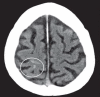

Background: Cerebral amyloid angiopathy (CAA) is a degenerative vasculopathy that is classically associated with lobar intracerebral or sulcal hemorrhage. Its prevalence is estimated at 30% in the seventh decade and 50% in the eighth and ninth decades. In this review, we summarize the risks linked to CAA with respect to the treatment and prevention of stroke.

Results: Among patients given systemic lytic treatment for stroke, those who have microhemorrhages tend to have a higher risk of treatment-associated brain hemorrhage. In a meta-analysis, 70% of patients who sustained a hemorrhage after thrombolytic therapy were found to have CAA, compared to only 22% in a control population. Patients with cerebral hemorrhages have microhemorrhages more commonly than patients with transient ischemic attacks (TIA) or infarcts. This was observed among persons under treatment with vitamin K antagonists (odds ratio, 2.7) or platelet aggregation inhibitors (odds ratio, 1.7). Moreover, the apolipoprotein E2 allele is associated with a higher incidence of intracerebral hemorrhage (ICH) under oral anticoagulation. Strict treatment of arterial hypertension can lower the risk of ICH in persons with probable CAA by 77%. On the other hand, the use of statins after a lobar ICH increases the risk for a clinically manifest recurrent hemorrhage from 14% to 22%.